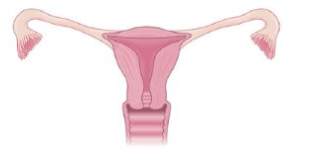

Utérus Normal